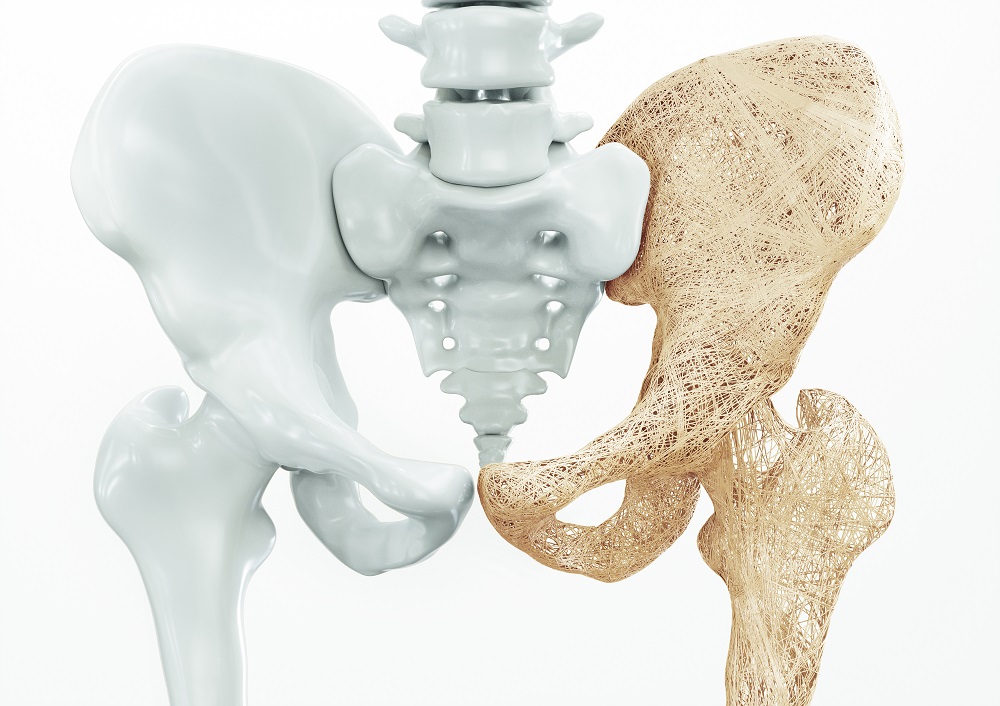

A osteoporose é uma doença assintomática, que causa enfraquecimento e porosidade nos ossos, e pode surgir com o envelhecimento. As principais causas da doença são a perda de cálcio ou a falta de vitamina D no organismo, que geram a perda de massa óssea. Isso pode causar um aumento do risco de fraturas até mesmo durante a execução de atividades simples do dia a dia.

O exame mais importante para avaliar a doença é a densitometria óssea, que mede a densidade do osso e a quantidade de cálcio presente nele.

O doutor Maeda acrescenta que as regiões mais acometidas pela osteoporose são vértebras (coluna), punho e quadril e alerta para a necessidade de procurar atendimento médico. “Quando as mulheres chegam no período da menopausa, elas devem realizar o exame de densitometria óssea. Nos homens, a descalcificação acontece mais tardiamente e, por isso, o exame é indicado a partir dos 70 anos de idade.

O tratamento é feito com reposição de cálcio e de vitamina D, por meio de dieta ou suplementação alimentar. Dentre as medicações utilizadas estão as que diminuem a perda de massa óssea (conhecidas como antirreabsortivos) e os formadores de osso (chamados de anabólicos). Para as mulheres, pode ser sugerida também a reposição hormonal. Os resultados devem ser acompanhados pelo médico, que também determinará o tempo de tratamento e a avaliação, feita sempre por meio do exame de densitometria óssea.